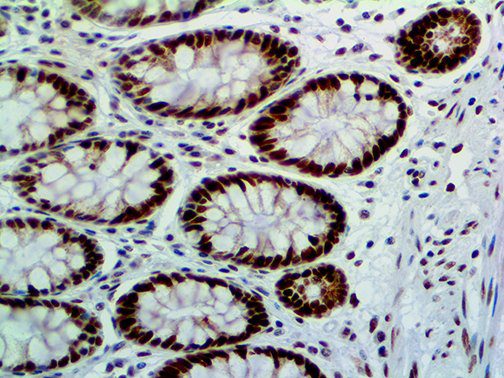

The first cytokines released are interleukin 1β (IL-1β) and tumor necrosis factor-α (TNF-α), which attract a variety of circulating white blood cells (WBCs) to the infection site, including neutrophils, monocytes, macrophages, and natural killer (NK) cells. This response, along with the antipathogenic chemicals released by these cells (i.e., complement), comprise the innate immune response. These cells directly attack the invading pathogen and also release additional cytokines, chief among them interleukin-1 and 6 (IL-6). IL-6 is essential for invoking the adaptive immune response, which calls T-cells, B-cells, and T helper (Th) cells to the infection site. IL-6 also stimulates further recruitment, proliferation and activation of macrophages.

This activation induces inflammatory monocytes to highly express IL-6, starting a localized and then systemic cascade effect that results in hyperproduction of IL-6, which accelerates the inflammatory process. Because IL-6 also increases vascular permeability, excessive levels cause blood vessels to become very leaky. This, along with clotting factors released from vascular endothelial cells, stimulates the coagulation cascade, resulting in microthrombosis (tiny clots), which leads to ischemia and tissue death of the kidney, intestines, heart, liver, brain and extremities.